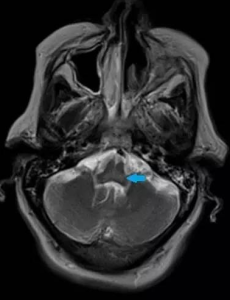

2.臨床表現:類似乙醇中毒,但患者呼出氣中無酒精氣味。多於誤服後數十分鐘至數小時出現症狀,輕者呈醉酒樣,重症病例表現為發作性神志模糊、昏睡、昏迷、抽搐、大小便失禁及腦水腫。抽搐呈強直-陣攣性發作,患者可有眼球震顫、視盤水腫等。患者進入昏迷狀態,可有低血壓、心動過速、呼吸急促、發紺。重症患者可有肺水腫、心臟擴大、充血性心力衰竭。個別患者有急腹症表現,並可出現不同程度的腎功能損害,重者可因急性腎小管壞死出現尿閉而死亡。